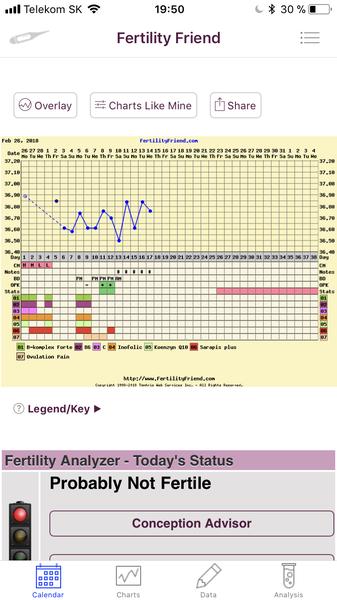

Grafy bazálnej teploty

Baby, nová téma o grafoch BT, ovulačných testoch, tehotenských testoch a hľadaní duchov je tu 🙂

Ak meriate bazálnu teplotu a zapisujete si hodnoty do grafov, ste na správnom mieste. Poradíme, pomôžeme, podporíme.

Grafy si môžete vytvárať na nasledovných stránkach:

www.fertilityfriend.com